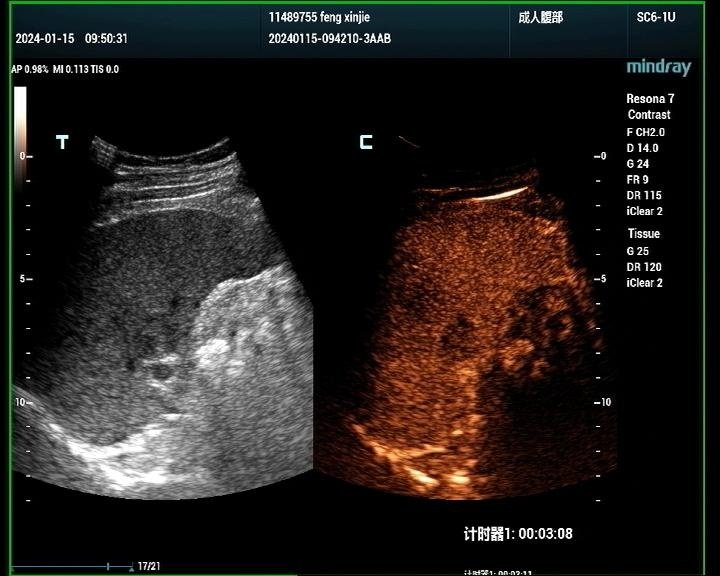

肝脏肿瘤分为良性和恶性,其中血管瘤是最常见的肝脏良性肿瘤,肝癌是最常见的恶性肿瘤。肝脏肿瘤超声影像诊断方面主要有肿瘤病灶的检出、对已检测肿瘤的定性诊断、肝局灶性病灶中肿瘤与非肿瘤病变的鉴别。超声造影对肝脏肿瘤的鉴别诊断主要是通过增强和动态增强方式观察肿瘤。

肝癌病例1